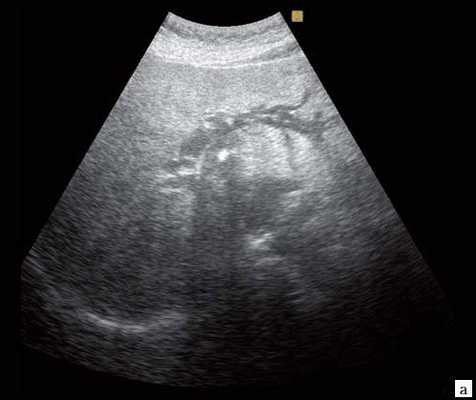

(Левый) На косом трансабдоминальном УЗ срезе в печени определяется умеренное расширение общего желчного протока и ответвляющихся внутрипеченочных протоков; эти изменения вызваны обструкцией протоков опухолью головки поджелудочной железы (не показана).

(Правый) При цветовой допплерографии у того же пациента отмечается отсутствие кровотока в расширенных тубулярных структурах, что указывает на то, что это и в самом деле расширенные желчные протоки. Следует выполнять цветовую допплерографию в повседневной практике для подтверждения дилатации желчных протоков.